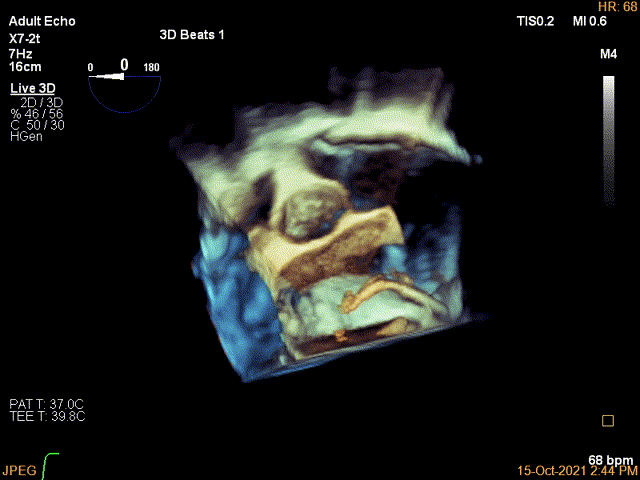

3D视图两个夹子近似并排排列,排列很紧密

(4)两个夹子尽量靠近,保持平行,在TEE 3D view和DSA 切线位确认夹子靠近的位置 和同向,瓣膜没有异常的抖动,证明张力合适,clip位置满意。